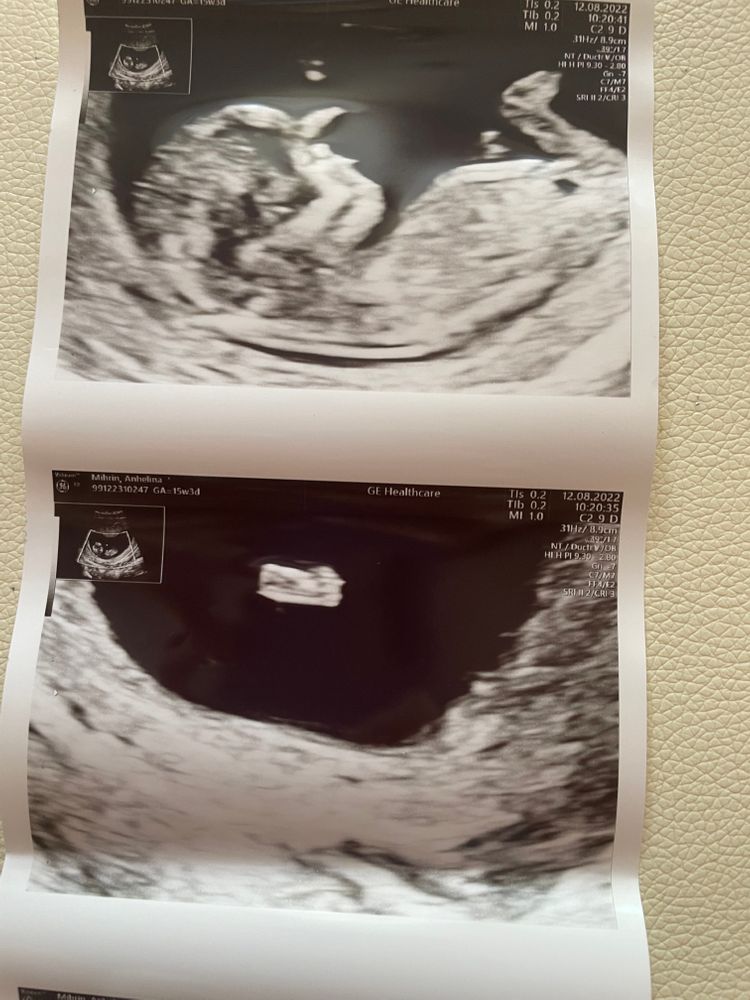

Первый скрининг 🥰

Срок: 11+5

Сегодня увидели нашего малыша. Он казался таким большим🥺 а на самом деле только 5 см🥰❤️

Все замеры в пределах нормы😍 Жалко только, что она даже не предположила пол.🤷🏼♀️ Ждём 21 недели и на 2 скрининг ❤️

Может кто-то сможет увидеть? Мне кажется, что мальчик 🤰🏼

А мне кажется, девочка, если половой бугорок - это то, что я вижу.

Больше похоже на девочку, половой бугорок не вверх, а прямо, прям параллельно.

Девочка скорее всего - половой бугорок горизонтально, у мальчиков он под бОльшим углом торчит.